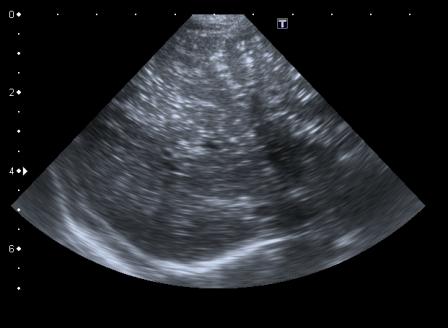

В продолжение темы - сходный случай. Ребёнок 5 мес, поступил с признаками энтеральной недостаточности и вздутым животом.

На рентгенограмме - множественные горизонтальные уровни в просвете кишки, контрастирования газа в проекции печени нет(к слову - иллюстрация того, что горизонтальные уровни в кишечнике не обязательно признак кишечной непроходимости, стул у ребёнка кашицеобразный за последние 12 часов - 4 раза)

На УЗИ - множественные гиперэхогенные включения в печени. Через 2 дня живот опал, на УЗИ - нормальная печень. Признаков некроза кишечника не было.

Рискну высказать предположение о возможности проникновения газа в портальную систему через неповреждённую, но восппалённую стенку кишки на фоне избыточного давления в её просвете .